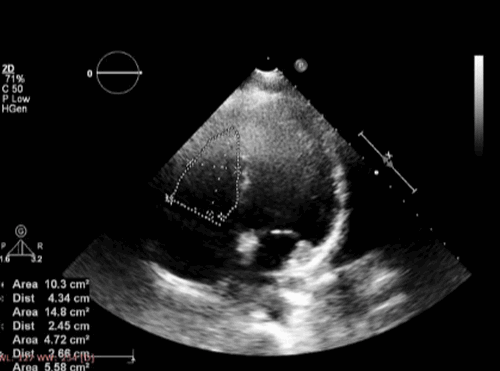

2. Фракция изменения площади сечения (ФИПС) ПЖ (Fractional area change): этот показатель легко определяется в апикальном четырехкамерном сечении.В конце систолы и диастолы в плоскости трикуспидального кольца проводится прямая линия, от которой очерчивается граница эндокарда.ФИПС просчитывается по формуле:

ФИПС (%) = (КДП - КСП)/КДП

КДП - конечно-диастолическая площадь

КСП - конечно-систолическая плошадь.